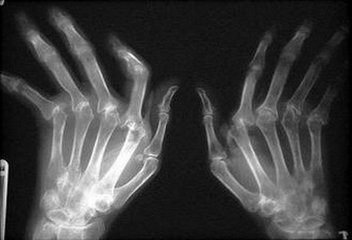

风湿性关节炎是风湿热的一种表现。风湿热是由A组乙型溶血性链球 ...

风湿性关节炎的危害,随着风湿性关节炎疾病的不断高发,在我们身 ...

众所周知,类风湿性关节炎在日常生活中比较常见,很多人都有一定 ...